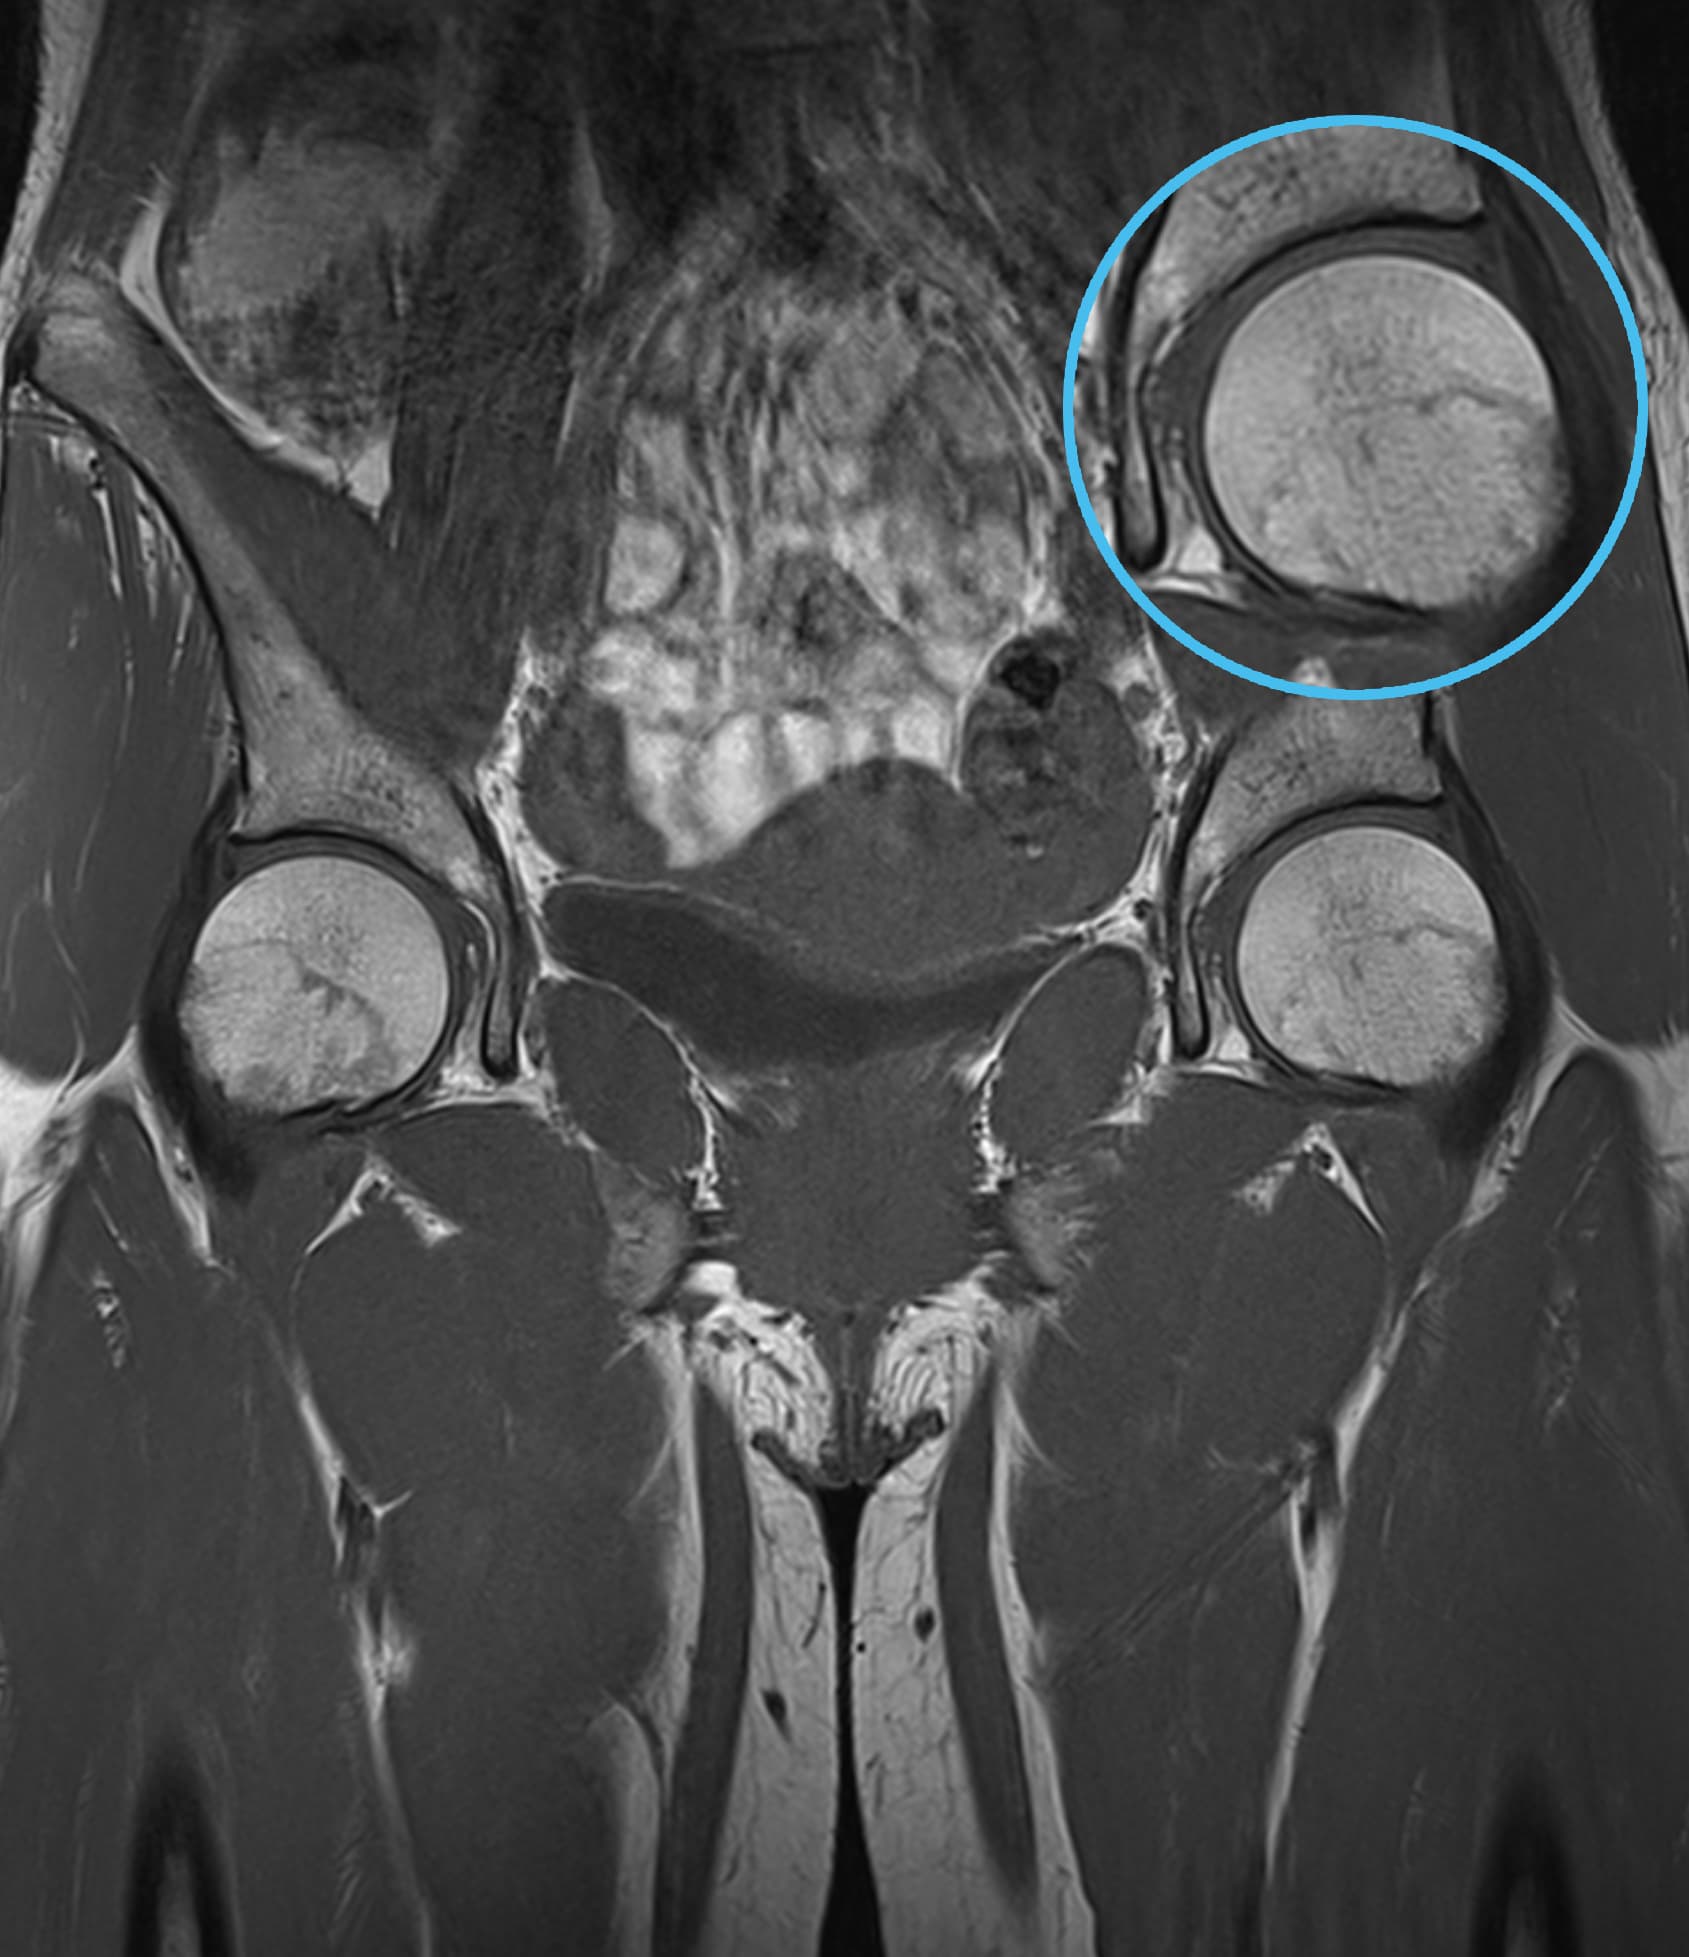

See real-world examples of SwiftMR™ across various MRI systems and anatomical regions

Scan time 03:14

Scan time 02:07

Scan time 03:08

Scan time 1:12

Scan time 04:53

Scan time 1:46